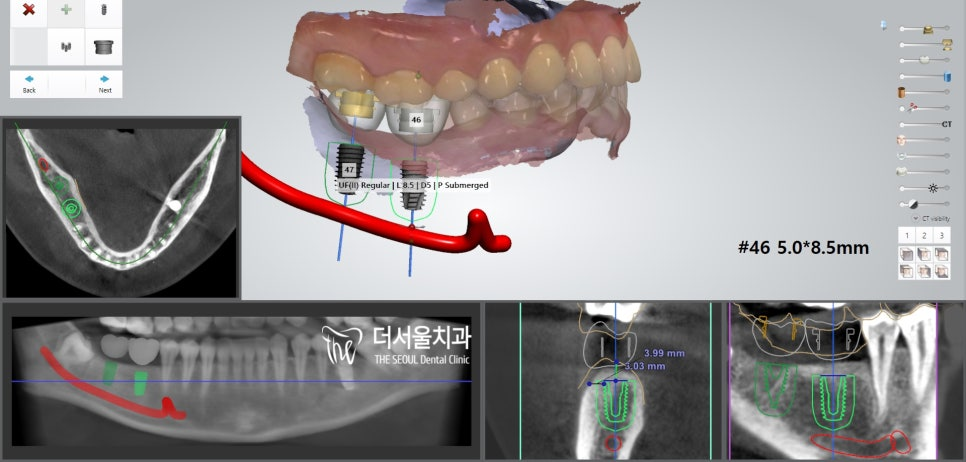

좌측과 마찬가지로 컴퓨터 분석을 통해

식립 위치 및 방향, 각도 등을 결정했습니다.

오랜기간 잔존치근만 남아있었기 때문에

치조골이 소실되어 있진 않을까 걱정이 되었는데요.

다행히 별 다른 문제 없이

식립을 도와드릴 수 있을 것 같네요.

별다른 문제 없이

치조골에 단단히 심어진 모습입니다.

픽스쳐를 심고 나서

치유지대주(healing abutment)까지 체결을 도왔습니다.